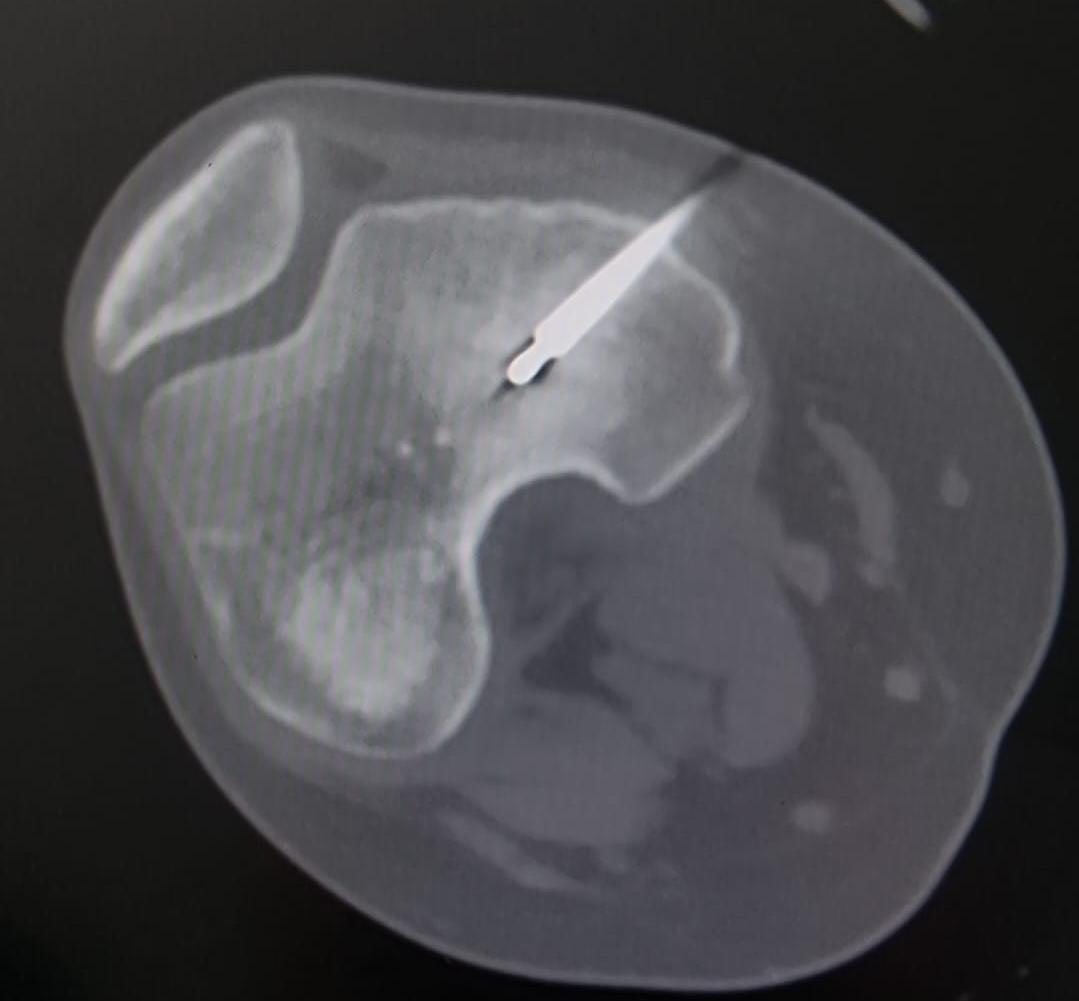

السوسنة - اجرى الكادر الطبي في مستشفى الأميرة بسمة عملية نوعية دقيقة لعلاج ورم عظمي حميد من نوع (Osteoid Osteoma) باستخدام تقنية الكي بالتردد الحراري (Radiofrequency Ablation) الموجهة بالأشعة المقطعية.

وتم إجراء هذا التدخل بنجاح من قبل الدكتور محمد نصر نزال والدكتور عثمان أبو قران أخصائيي الأشعة التداخلية وقسطرة الأوعية الدموية وبإشراف ومتابعة الدكتور عمر سميرات (أخصائي عظام الأطفال).

وبين الفريق الطبي أن خصوصية هذه الحالة تكمن في عمر المريضة (14 عاماً) حيث استقر الورم مباشرة على صفيحة النمو (Growth Plate) في عظم الفخذ البعيد. وتعتبر هذه المنطقة من الحساسية بمكان إذ ان أي خطأ قد يؤثر على النمو المستقبلي للعظم ما جعل استخدام تقنية الكي الحراري تحديا كبيرا يتطلب دقة فائقة لتجنب إلحاق أي ضرر حراري بالأنسجة المحيطة.